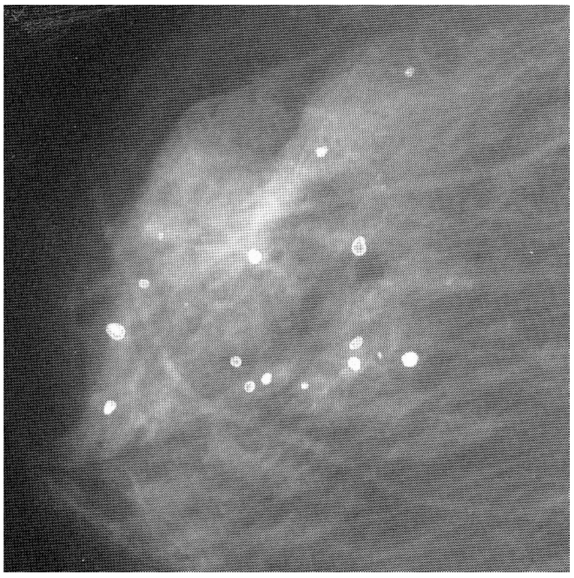

Ca and its compounds are always present in milk ducts. Mammography is unable to distinguish these mere calcifications from a microscopic cancerous lump. See, for example, Figure 1 [Fig. 1]. This is a mammogram of a female breast, revealing calcified tiny tissues (white dots). An appreciable number of the calcified dots are malignant, and prone to spread into the immediate vicinity. This mammogram does not identify which calcified dot is malignant. What’s worse, the breast cancer in the younger generation does not always entail the calcification. Mammography is powerless to detect such a non-calcified cancer.

Figure 1: A mammogram of female breast, revealing micro-calcifications (white dots) [6], reproduced with permission